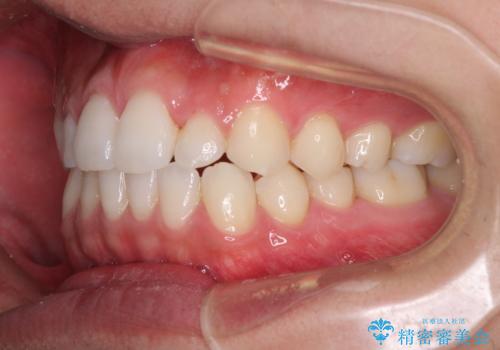

前歯のデコボコとクロスバイト インビザライン矯正治療

- 前歯のデコボコとクロスバイトを治したいとのことで来院された患者様です。

上下顎ともに歯列全体の側方拡大を行い、下顎前歯はIPR(歯と歯の間を削る)によってデコボコとクロスバイトが解消するように設計し、インビザラインにより治療を行うこととしました。